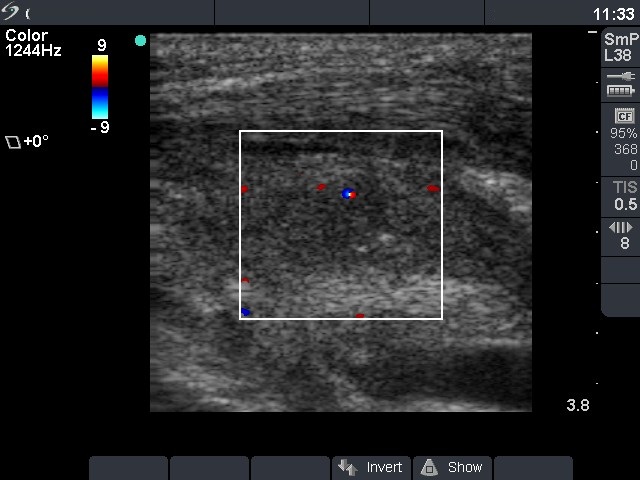

Rare forms of thyroiditis - Case 6: Subacute thyroiditis-like reaction after ethanol sclerotherapy

Subaute thyroiditis-like reaction - 8 days after previous session (ultrasonographic picture 4)

Right lobe, longitudinal scan, power Doppler mode. Type 1 vascular pattern.